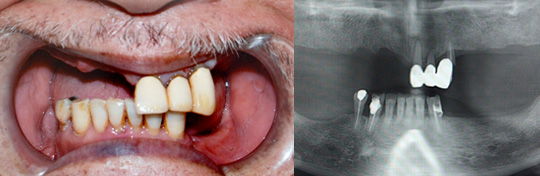

All-on-4(6)

総入れ歯の方や多くの歯を失った方に、4~6本のインプラント体をバランスよく骨に埋入する手術のことです。

顎骨に傾斜角をつけてインプラントを埋入し、すべての歯を4~6本のインプラントでしっかり固定するため、治療したその日に噛むことができ、普通の食事が可能です。

通常上顎・下顎共8本程度のインプラントが必要になりインプラントの本数が多い分費用もかかりましたが、All-on-4(6)は片顎12本の人口の歯を支えるために必要なインプラント本数を4~6本に減らすことが可能になり、手術時間や費用を抑えることが可能になりました。

【治療前】

【治療後】